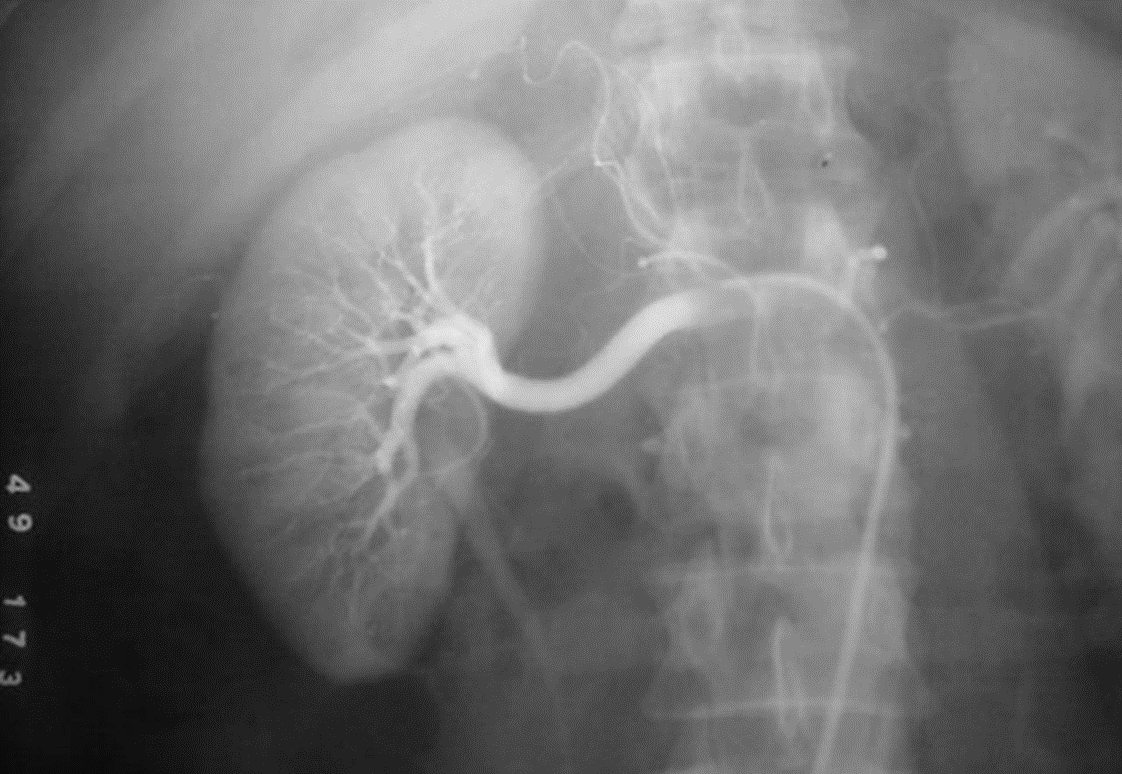

Renal arteriography is performed via a catheter introduced into the femoral artery by the Seldinger technique.

Selective injections are made into one or both renal arteries.